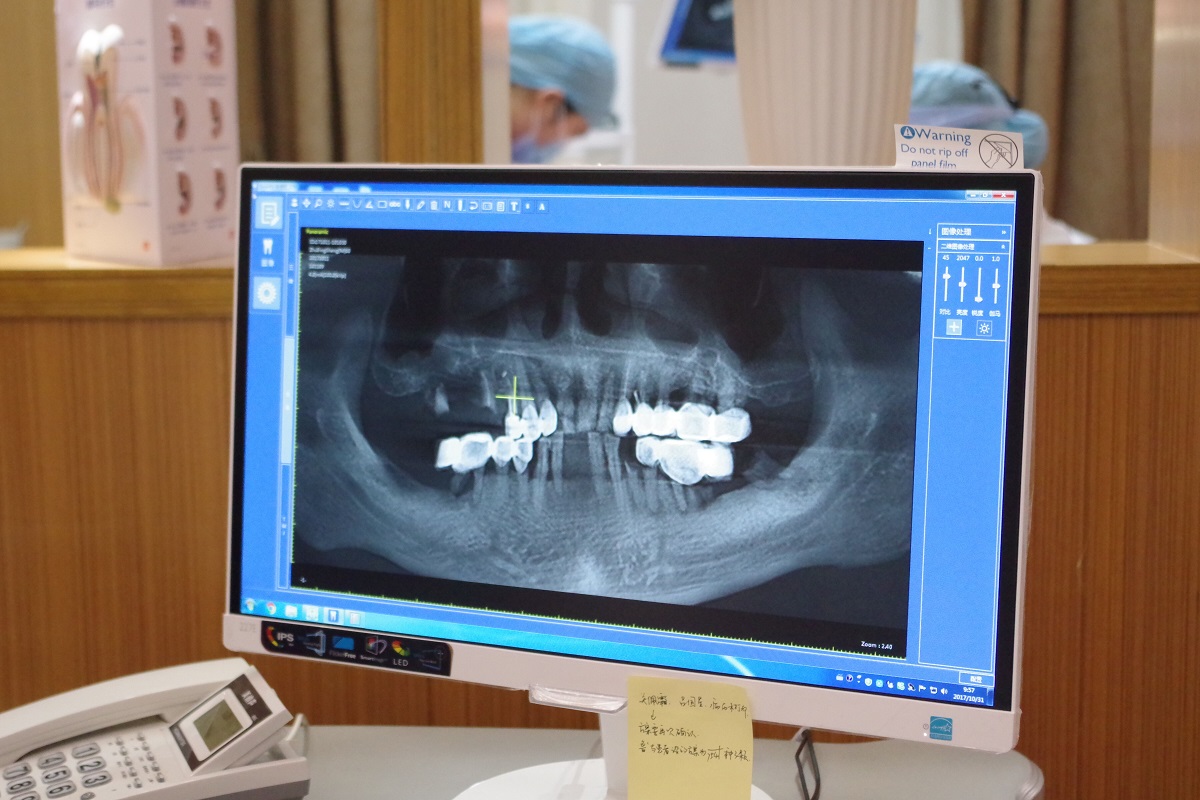

數字化舒適種牙,年前種牙立享美食

順德德倫口腔醫院技術院長林智勇為炳叔設計了數字化種牙方案,并在計算機的引導下準確植入6棵植體。“并非9顆缺牙就要種9顆種植體,采用數字化種植牙的方式,只給炳叔種了6顆植體,然后通過搭橋的方式實現9顆牙齒的作用,避免每一個牙位都種植的缺陷,也能讓老人家少受痛苦。”林智勇解釋道。